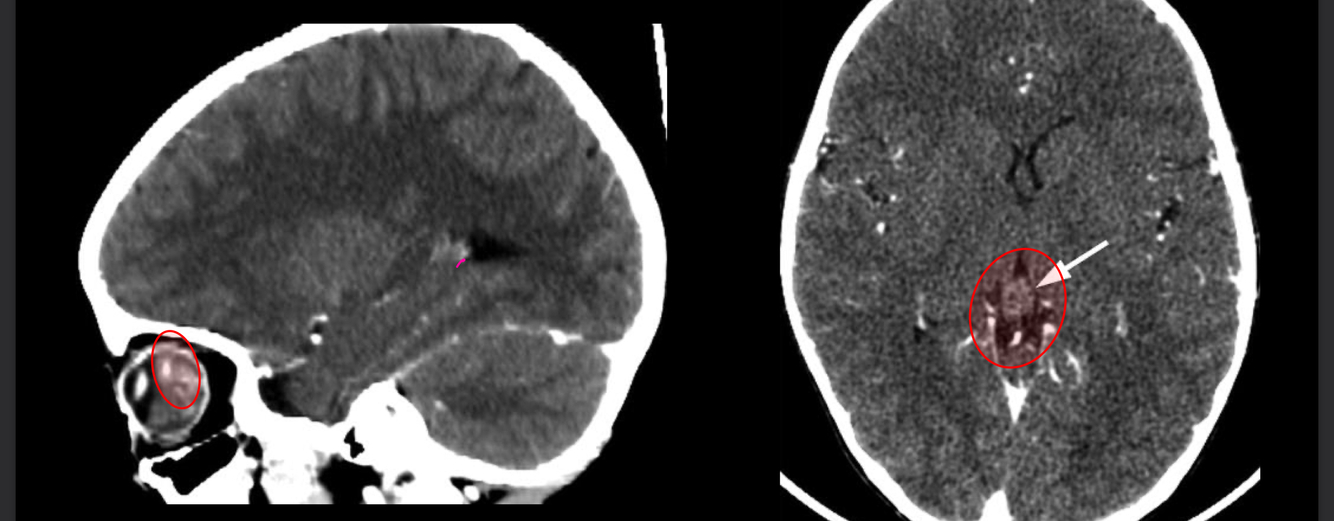

13

Q

Que se obsevra?

A

Tc Retinoblastoma trilateral

* Calcificación en ojo

* Capta contraste

* Tumor pineal

17

Que es?

Tc y RM de desprendimiento de retina

Hiperdensidad y hiperintensidad

fluido subretinianio

neoplasias

trauma

retina triangular